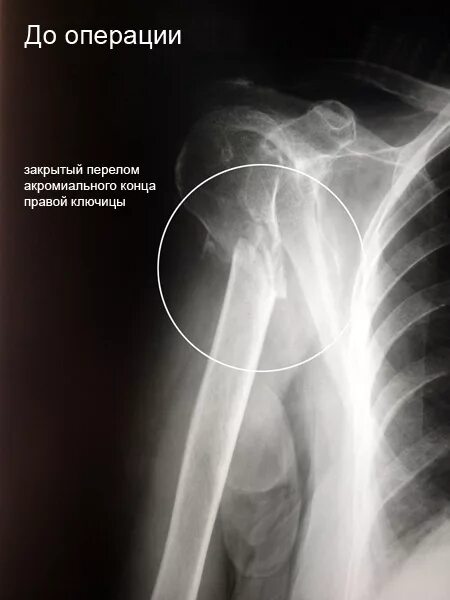

Операция при переломе шейки плеча